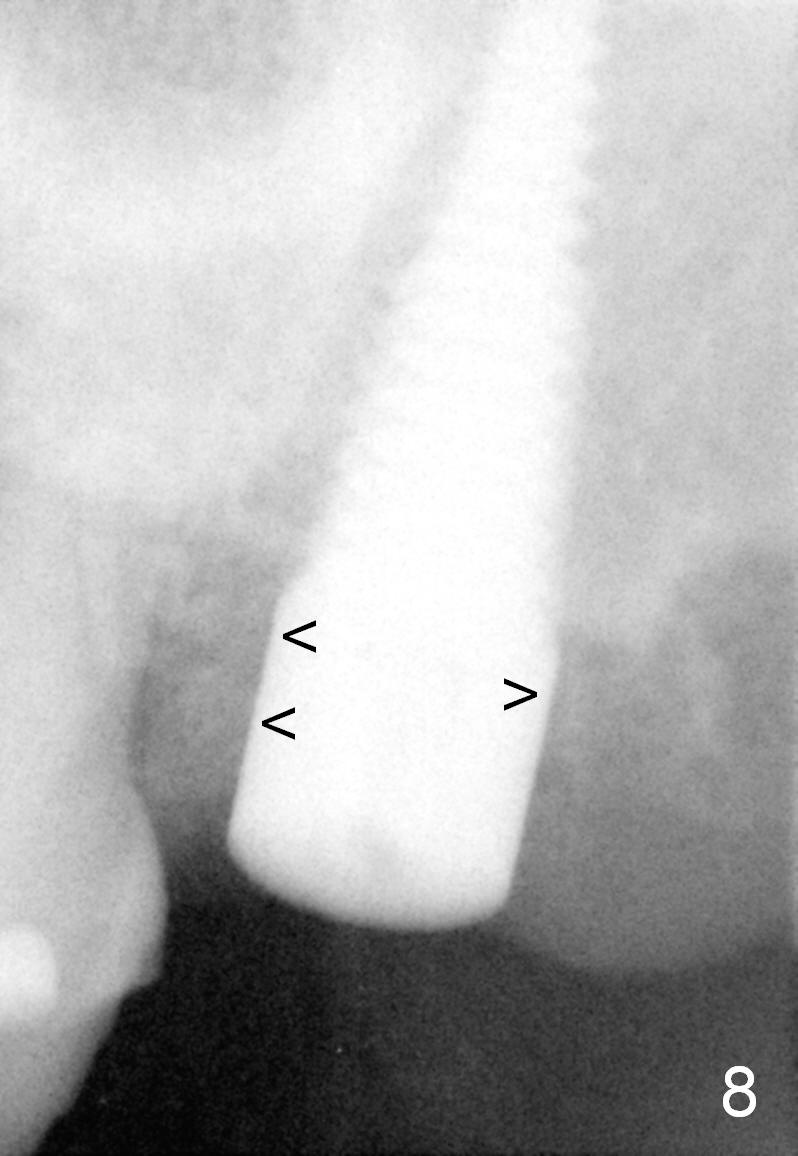

The mesial and distal socket spaces apparently disappears 3 months postop (Fig.8).